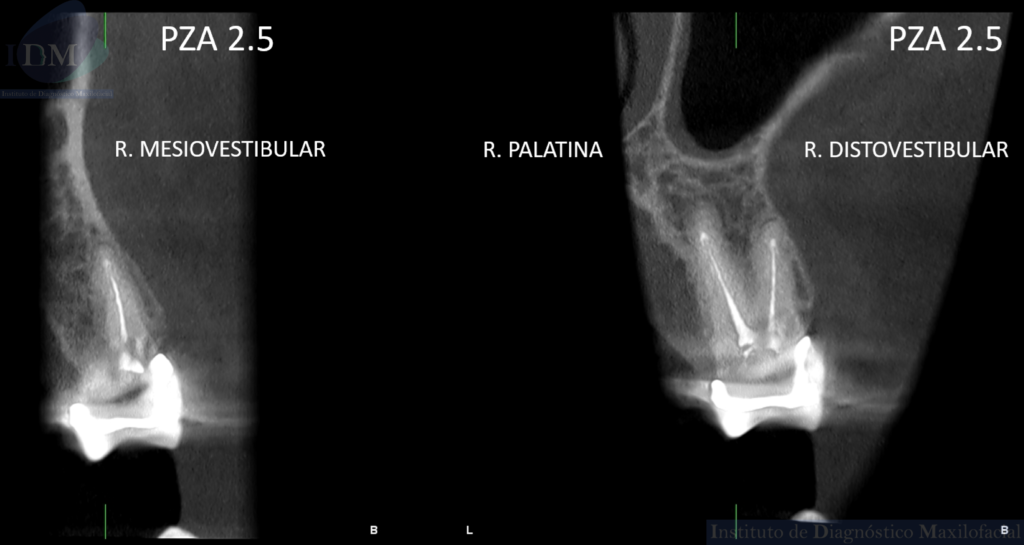

Así mismo en la tomografía volumétrica de haz cónico localizada se evidencia como hallazgo imagenológico, la presencia de tres segmentos radiculares con material de obturación de conductos en la pieza 25. Siendo dos raíces vestibulares (mesial y distal) y una raíz palatina.

CORTES TANGENCIALES

- Premolar con tres segmentos radiculares.